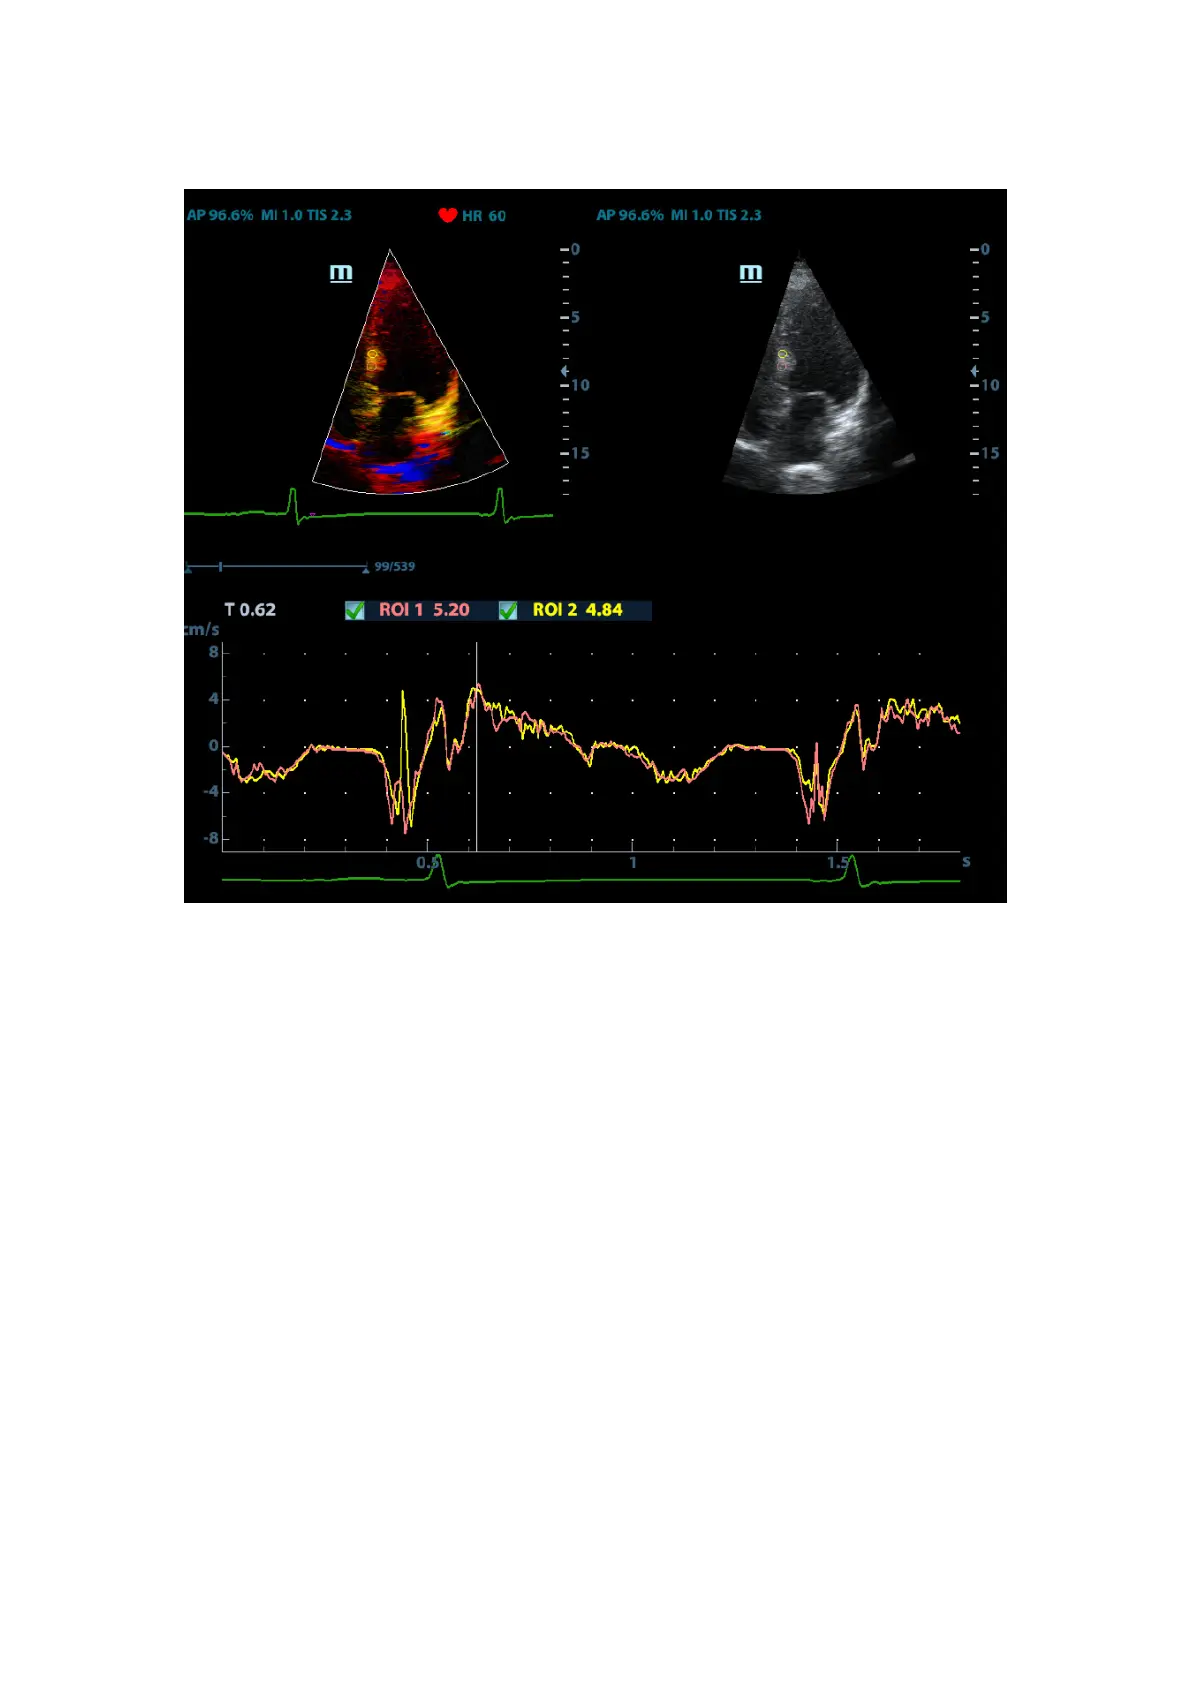

5.8.4.1 TDI QA Screen Description

1---TVI Cineloop window

Sample area: indicates sampling position of the analysis curve. The sample area is color-

coded, 8 (maximum) sample areas can be indicated.

2---B Cineloop window

3---Displays analysis curve

z Y axis represents the velocity (unit: cm/s), while X axis represents the time (unit:

s).

z Frame marker: a line that perpendicular to the X axis, can be moved horizontally

left to right (right to left) by rolling the trackball.

z Click the check box beside the ROI to set if to hide or to display the TIC curve.

4---Displays ECG trace.

1 2

3

4